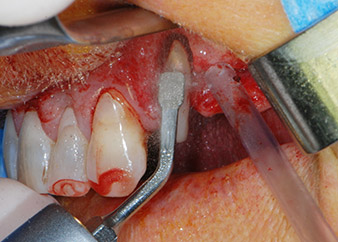

However, we maintained our initial plan to retain both teeth as temporary bridge abutments during the six-months osseointegration period of the implants. At reentry, the situation would have to be reassessed. First, in an attempt to manage the endo-perio problem, the remaining root surface was carefully debrided with piezoelectric equipment (Piezomed, W&H, used with the spatula-shaped insert S1, originally designed for erosion of the lateral sinus wall) (Fig. 4).

Then the apex was abraded with the same instrument to remove residual infected apical tissue and to reduce possible accessory root-canal ramifications (apicoectomy) (Fig. 5). A retrograde filling was not necessary because the orthograde filling had just been revised.

periodontium

Fig. 4: To preserve the tooth as a temporary abutment, the periodontium was debrided with piezoelectric equipment …

buccal apex of tooth 24

Fig 5: ... and the buccal apex of tooth 24 was abraded with the same instrument (apicoectomy).